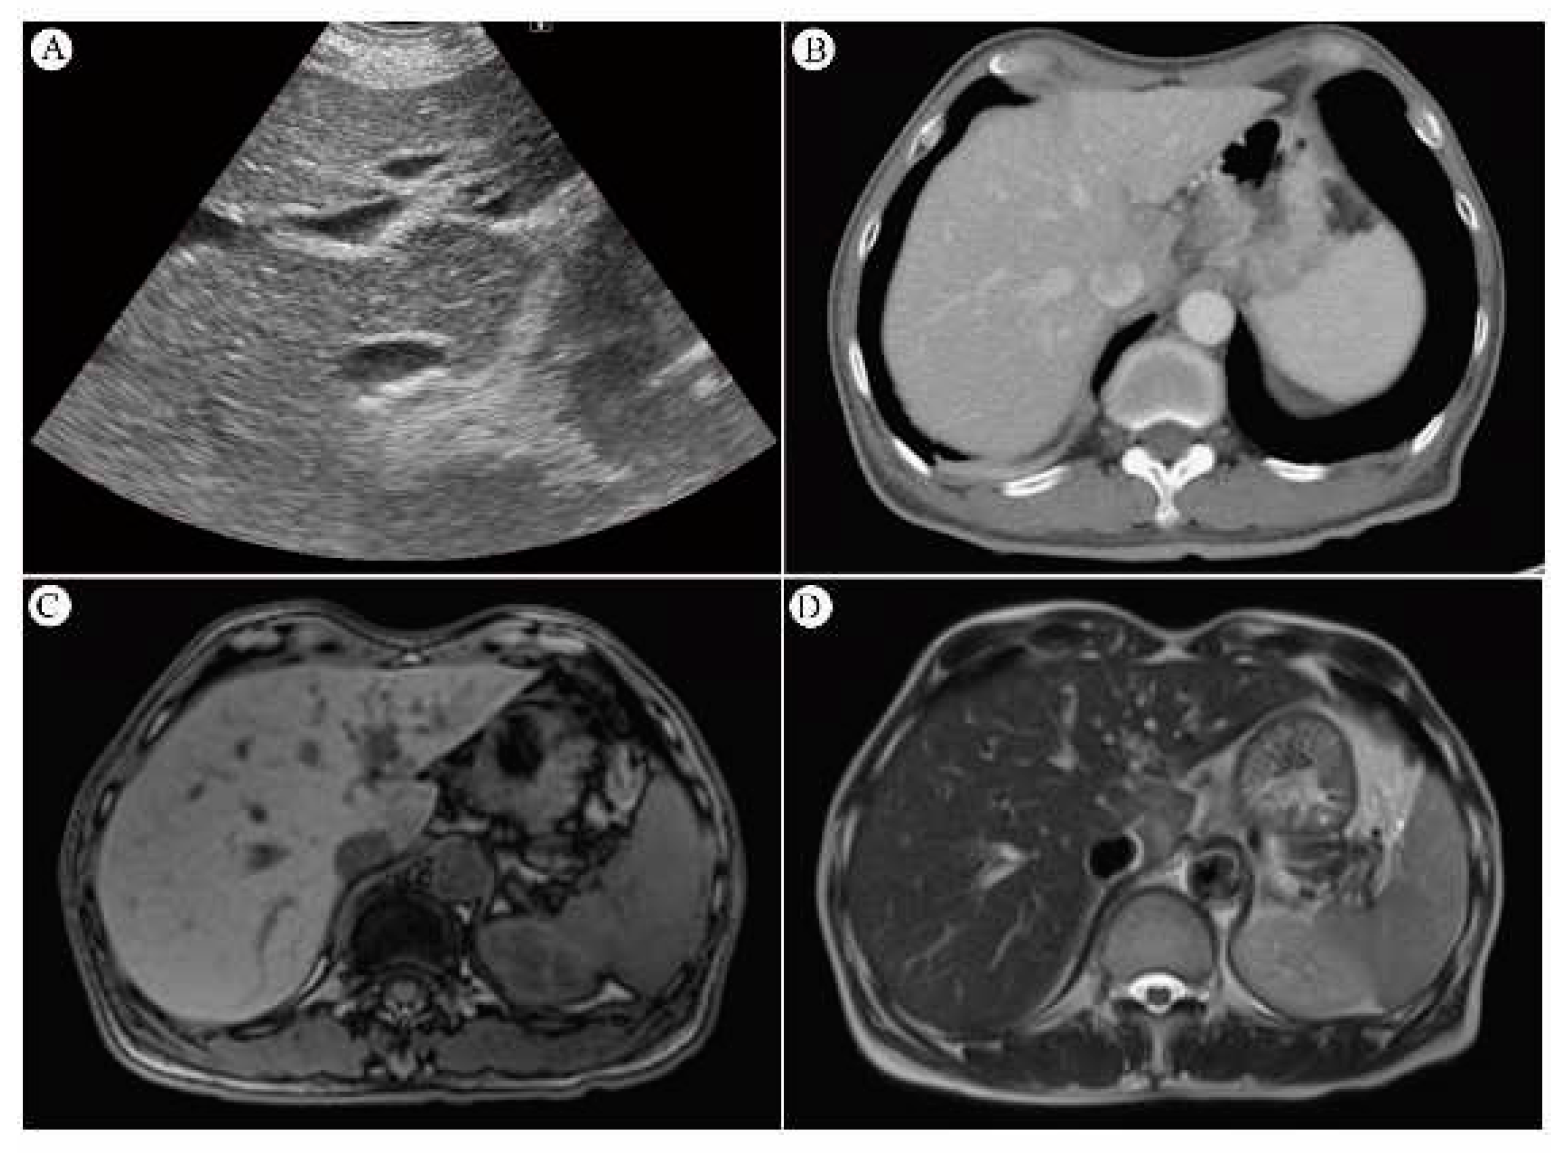

4.7.1. Sono of Liver and Its Sensitivity

4.7.2. CT Scan and Its Sensitivity

4.7.3. MRI and Its Sensitivity